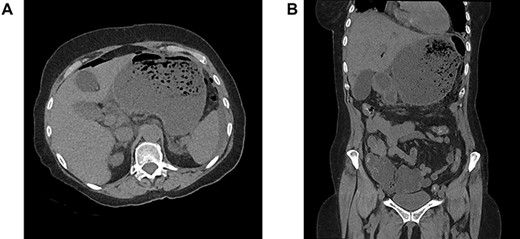

A 64-year-old woman was admitted in emergency for severe abdominal superior pain, nausea, dysphagia and fever. She explained having undergone a Nissen fundoplication 2 weeks earlier at another hospital, complicated a few days later by persistent dysphagia leading to redo-laparoscopy. Past medical history included hypertension, chronic obstructive pulmonary disease, hypothyroidism and appendectomy. On physical examination, she was septic (38.2°C, 110/70 mmHg, 110 bpm) with diffuse abdominal guarding. The blood test revealed a high grade of inflammation (C-reactive protein 17.35 mg/dL, white blood count 20.9 1000/mm3, lactic acid 3.2 mmol/L). The computed tomography scanner showed signs of perforation with hugely dilated stomach (Fig. 1A and B). Laparoscopic exploration attested to a generalized purulent peritonitis. Surprisingly, we found also a gastric greater curvature plication leading to a pyloric obstruction (Fig. 2A and B). Dismantling the Nissen wrap and the gastric plication allowed to find the gastric perforation on the top of the wrap (Fig. 3A and B). Simple closure of the perforation and large peritoneal lavage were performed. Postoperative recovery was marked by a left subphrenic abscess resolved under antibiotherapy. The patient was discharged on postoperative day (POD) 22.

(A) gastric greater curvature plication, (B) pylorus obstruction.